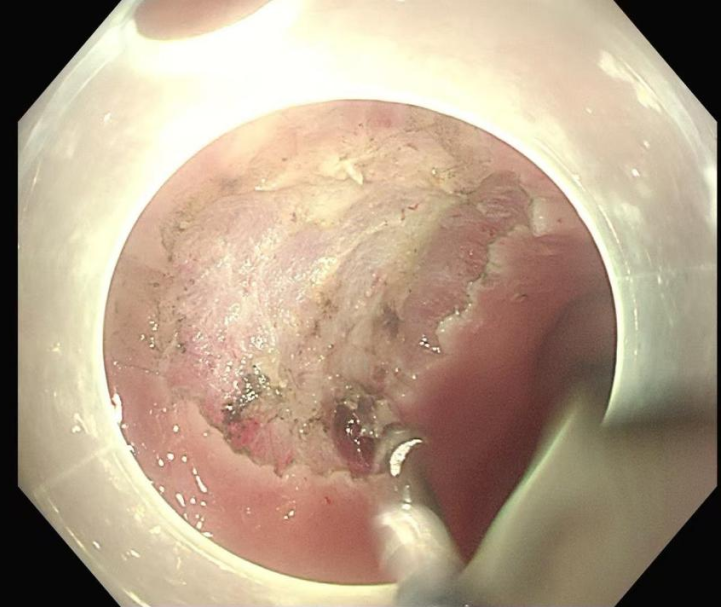

手术过程中,申星杰教授与医院内镜团队密切配合,操作精准高效,仅用 30 分钟便一次性完整切除张女士直肠黏膜病变部位。术后,张女士病情稳定,未出现任何手术相关并发症,目前恢复状况良好。

图解手术过程